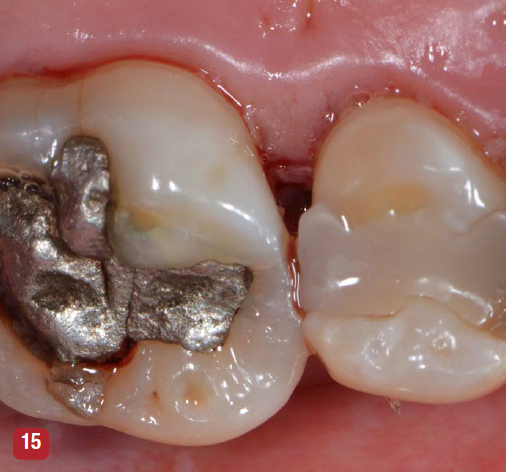

For an interproximal lesion on natural teeth, a single vertical mattress suture is placed at the base of the papilla using 4-0 or 5-0 suture material of the surgeon's choice. For implants, a similar vertical mattress suture is placed on the mesial and distal of the implant. Chromic or plain gut suture was used in the published university-based studies.8-11 Suture placement is shown in Figure 15. The purpose of the suture is to stabilize the base of the papilla and is not designed to close the mesial-distal incision. Care should be taken to not place the suture at the thin tip of the papilla or reflected tissue. Placing the suture in the thin portion of the papilla is associated with increased soft-tissue recession. The soft-tissue edges of the incision are approximated using finger pressure on a saline-soaked gauze. A closed VMIS incision is shown in Figure 15. Complex suturing, as is used in the papilla preservation suturing technique, is not necessary and may be detrimental to soft-tissue retention.